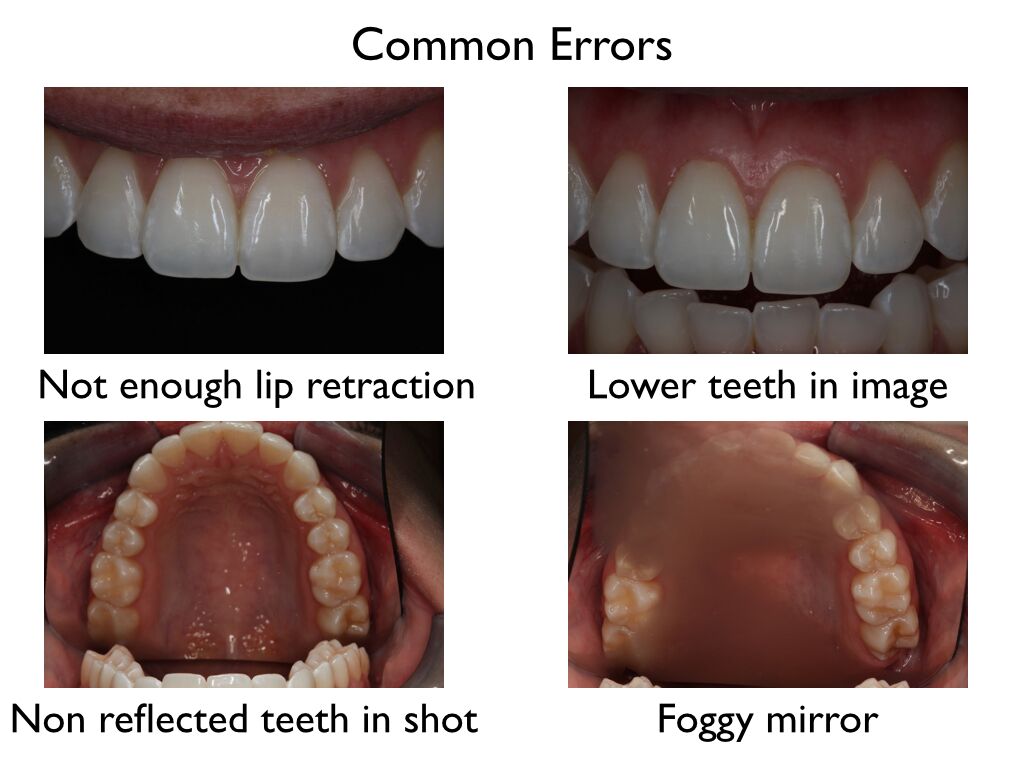

intra oral photos Digital dental photography

Tips For Exquisite Intra-Oral Dental Photography

www.clinicalmastery.comintra oral exquisite

www.clinicalmastery.comintra oral exquisite

Dental Photography Basics - Dental Photography Techniques - Intra-oral